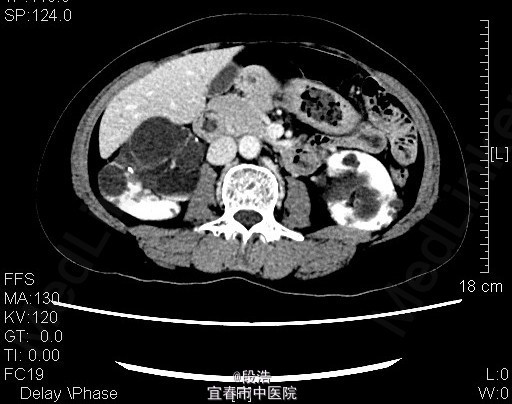

1、中年女性,体检发现双侧肾囊肿2年 2、患者于2年余前至当地医院体检发现双侧肾囊肿,当时诉腰部稍酸胀,尿量稍增多,无尿频、尿急、尿痛,无排尿困难,无血尿、脓尿等。起病以来,患者一般情况尚可,体重无下降

3、查体:未见明显异常 4、辅助检查:2013-4-11我院中腹部CT结果考虑多囊肝(未给出图像),双侧多囊肾,双肾囊壁部分钙化;双肾多发结石。2015年5月复查结果同前。

5、诊断:多囊肝,双侧多囊肾,双肾多发结石 6、入院后完善相关检查,生化,心电图,胸片未见异常,复查ct提示多囊肝,双侧多囊肾,双肾囊壁部分钙化;双肾多发结石,排除手术禁忌症后,行腹腔镜下左肾囊肿去顶术,术后予“注射用头孢美唑钠(先锋美他醇)”抗感染、抑酸、静脉营养补液等处理,术后恢复良好,顺利出院。术后半年复查再决定另一侧的处理方式。

7、多囊肾有两种类型,常染色体隐性遗传型(婴儿型)多囊肾,较罕见;常染色体显性遗传型(成年型)多囊肾,常于青中年时期被发现。中年发现的多囊肾病人,约半数有多囊肝。囊肿去顶术能够减轻囊肿对肾实质的压迫,保护剩余肾单位免遭挤压和进一步损害,使肾缺血状况有所改善,部分肾功能单位得到恢复,延缓了疾病的发展。多囊肾患者双侧均应手术,一般双侧手术的间隔时间为半年以上。晚期病例如已有肾功能损害处于氮质血症、尿毒症期,不论是否合并有高血压,减压治疗已无意义,手术打击反可加重病情。